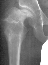

- Hospital Day 6: Respiked to 103.4. R hip Xray showed a defect in proximal

medial metaphysis, Possible osteomyelitis. The child was than taken to

the operating room for Incision & Drainage of Right hip via anterolateral

approach with suction irrigation system (seropurulent fluid drained).

- Post Operative Day 7: Drains removed. Respiked to 101.6. R hip Xray:

suggestion of demineralization of proximal metaphysis. The hip was reaspirated

and pus was obtained. Cultures neg.